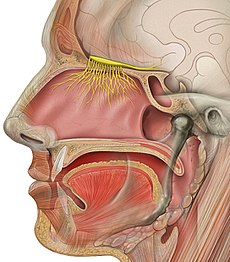

قیمت: 68٬000 تومان - دسته بندی فایل: پاورپوینت

قیمت: 68٬000 تومان - دسته بندی فایل: پاورپوینتپاورپوینت آناتومی بینی

فروش ویژه پاور پوینت حرفه ای آناتومی بینی با تخفیف استثنایی فقط 72 هزار تومان تعداد اسلاید: 38 اسلاید